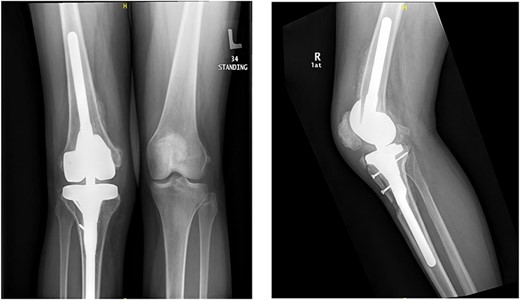

The patient lost some of her range of motion (ROM) in the post-operative period even with extensive physiotherapy. On her 4-month follow up appointment; ROM was 10–80°, which she sustained afterward. Plain radiographs continued to show no new HO formation at 4 months (Fig. 5).

Knee X-rays at 4 months visit continued to show no new HO formation, and continuation of healing of the osteotomy.